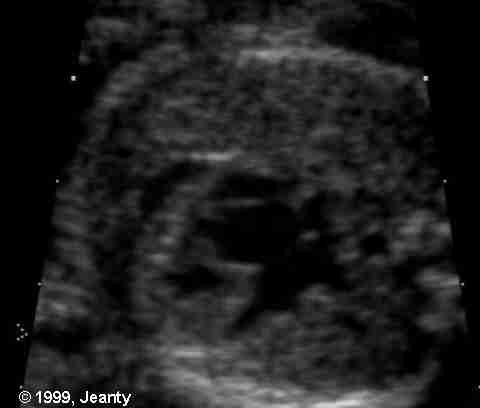

Figure 44g-3:

HLHS 4 chamber echocardiographicview slide showing the small

left ventricle (star), the large right atrium, right ventricle

and the left atrium.

Figure 44g-5:

Hypoplastic left heart syndrome in a fetus with a cephalic presentaton,

Transabdominal US image(four-chamber view) shows that the left

ventricle is small relative to the right ventricle and the left

atrium is small relative to the right atrium. Arrow= spine.

Figure 44g-6:

Large right atrium and ventricle compared to the left side.

(From Dr. Philippe Jeanty and others, 2004).

Figure 44g-7:

HLHsyndrome. From Dr. Philippe Jeanty,

1999.

Figure 44g-8:

HLH with VSD change. From Dr. Philippe

Jeanty, 1999.